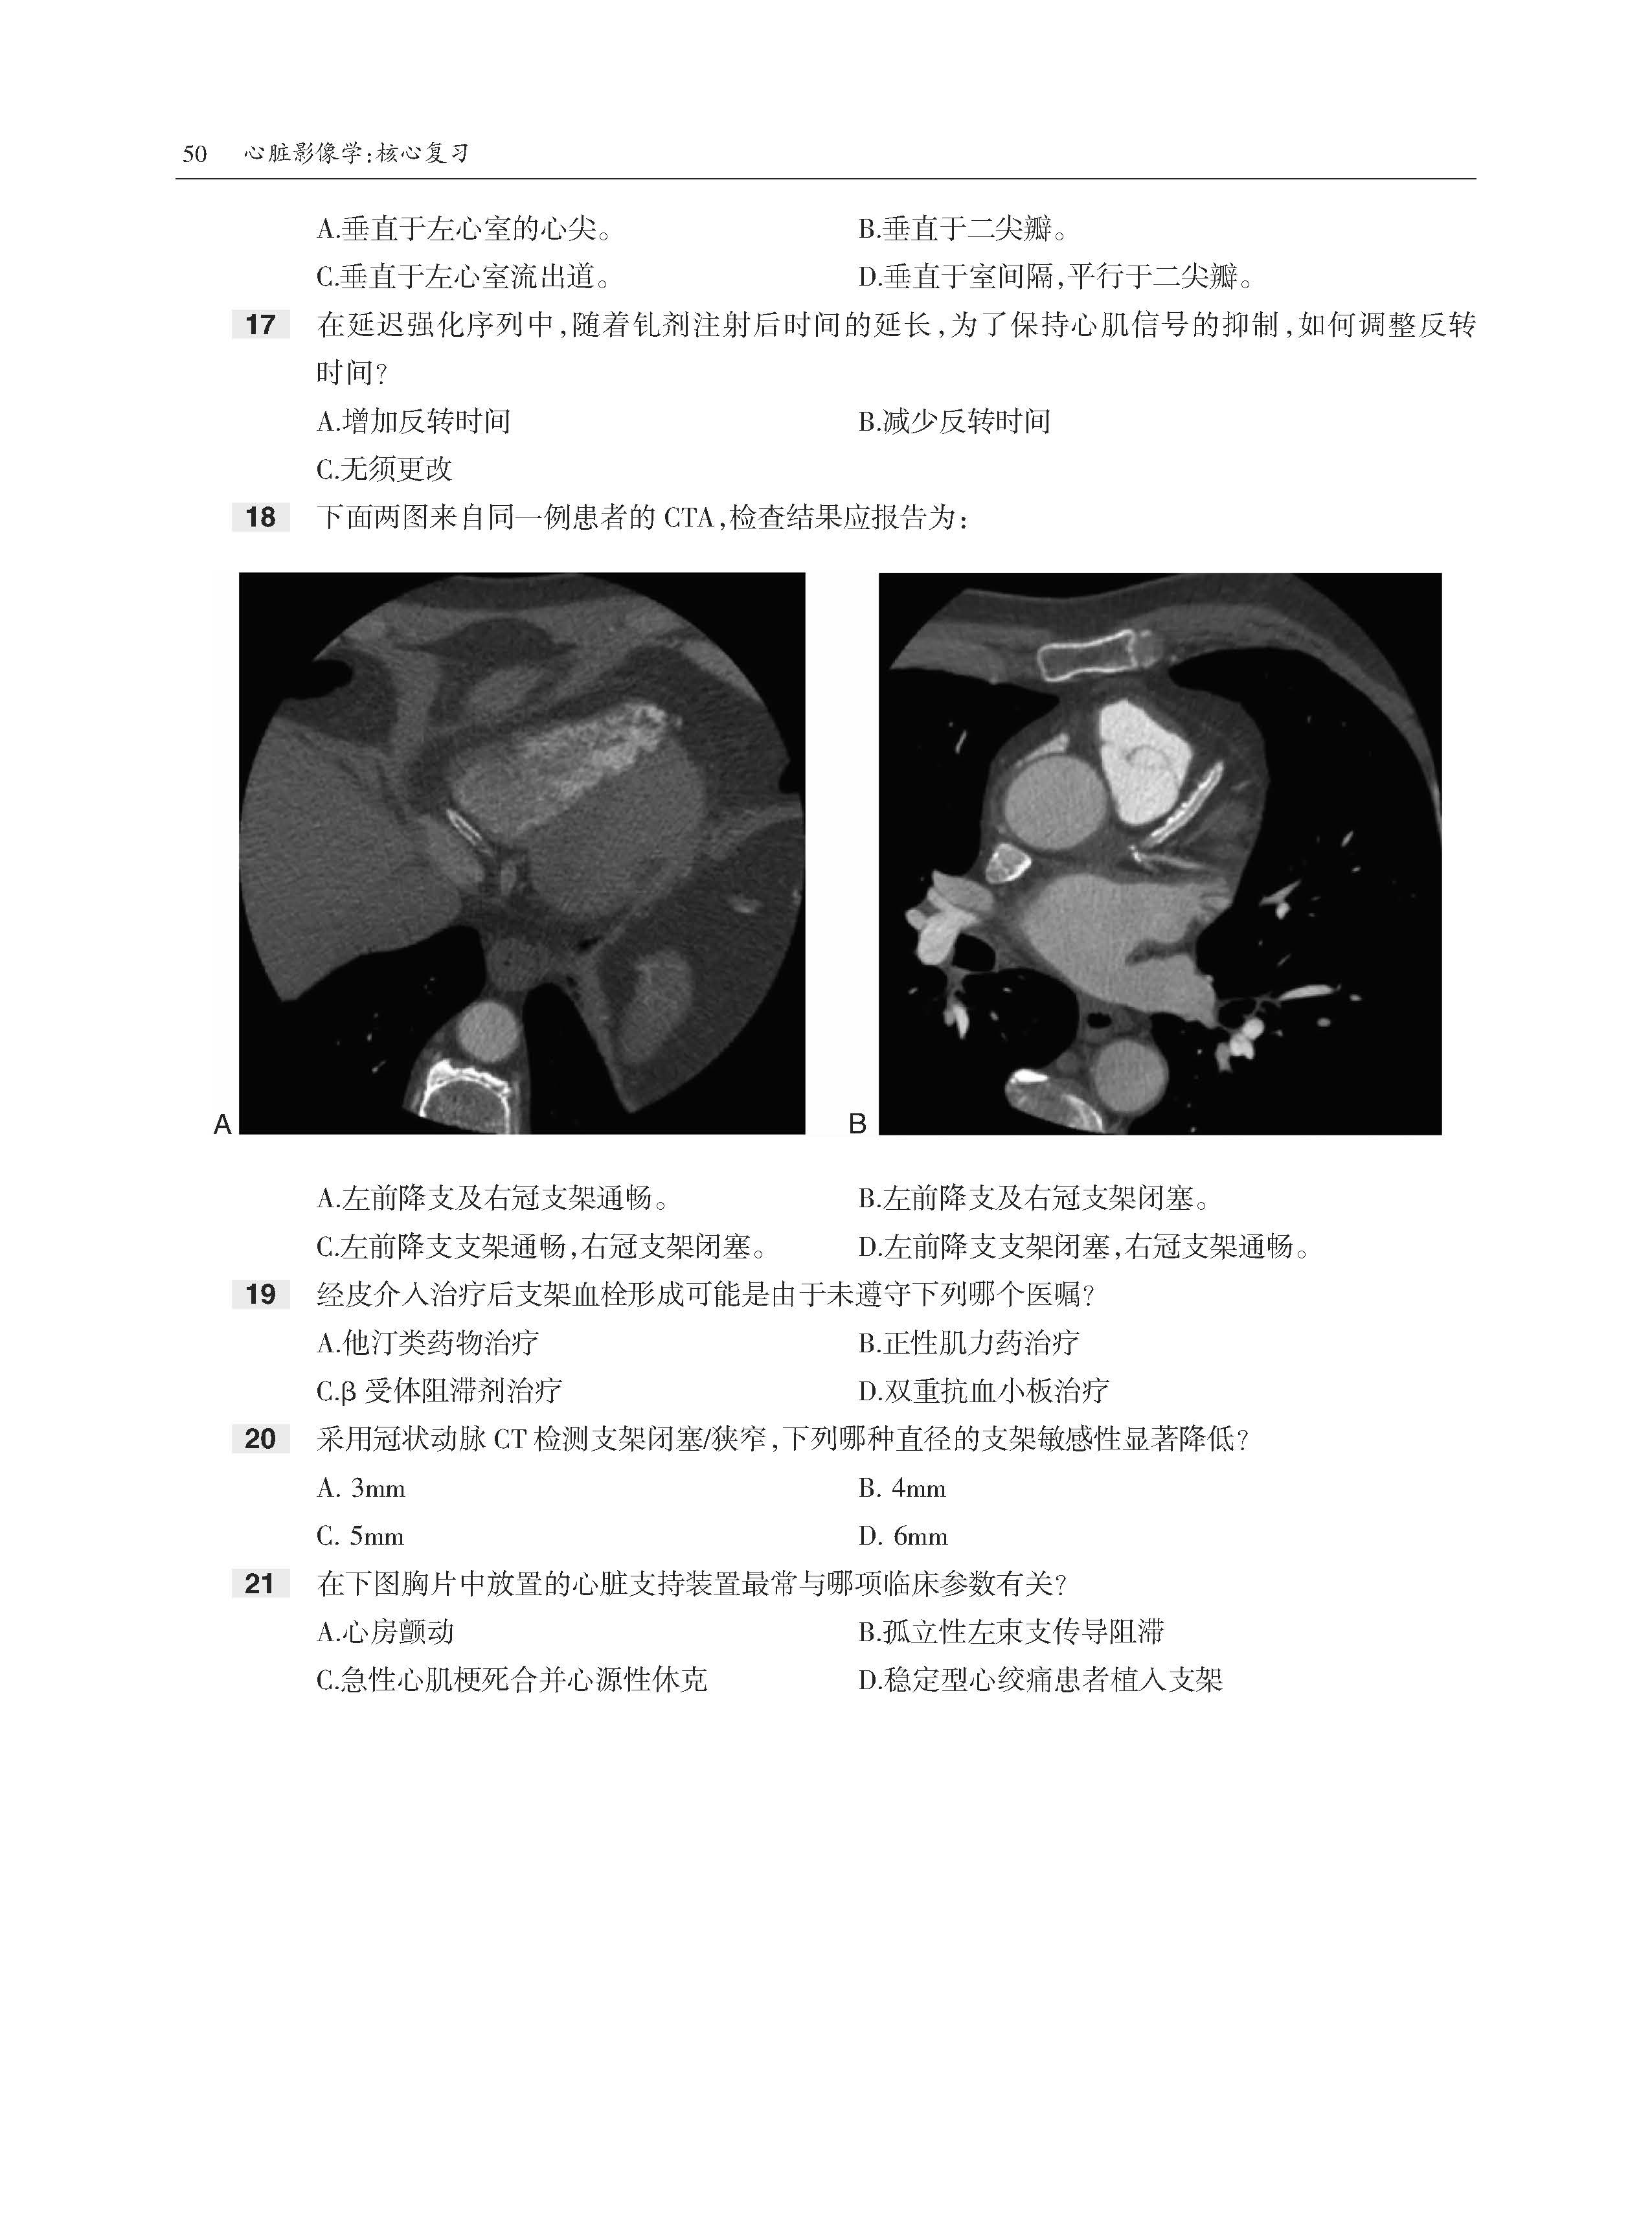

全书共11章内容,首先介绍了心脏放射成像基础和生理学基础,然后分别论述了缺血性心脏病、心肌病、心脏肿瘤、瓣膜病变、心脏周围病变、先天性心脏病、胸主动脉和大血管获得性病变,以及设备和术后表现。书中内容采用问答体例,各章开始均先给出患者影像图片和问题,供读者分析解答。在每章末尾给出问题答案,供读者参考。此书最大的特点是基于临床问题的多项选择题形式,每个选择题附有详细的解答,正确选项和错误选项均有详细的注释。该书全面回顾了心脏影像学的诊断要点,有助于读者理解和系统掌握心脏病变影像特点和诊断思路。

·300多道选择题,每道题都给出了答案、解析和相关参考文献。

·大量高清图像,直观展示病变。